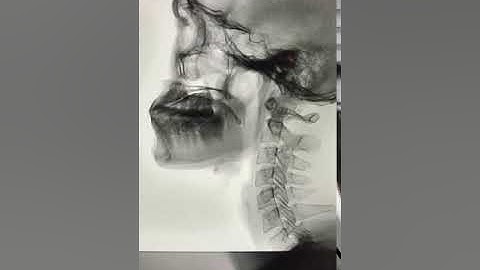

X QUANG TIÊU HÓA CẢN QUANG